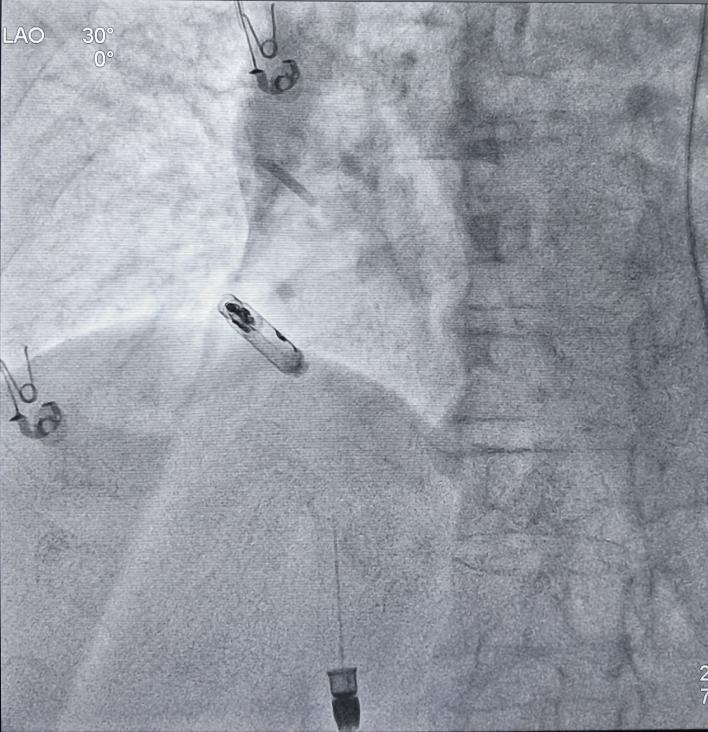

最终植入位置

手术过程十分顺利,手术团队通过精细、精准的操作,将仅有传统起搏器十分之一大小的新型无导线起搏器输送至右心耳,利用其特有的用于心房起搏的双螺旋设计,起搏器被牢固地锚定在右心耳基底部。整个手术过程顺利,耗时仅约30分钟,术中及术后参数测试均十分优异、显示起搏器工作状态良好。